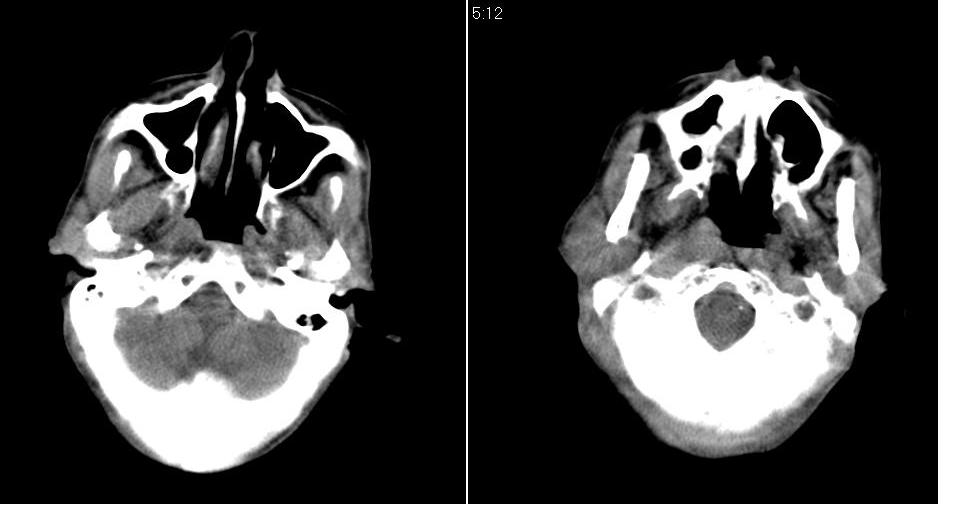

男 70岁,右侧颈部包块八个月余,下午及夜间疼痛加剧,包块质硬。化验穿刺镜下可见大量成堆裸核上皮细胞,可符合结核性淋巴结炎。

右侧颈部不规则软组织密度肿块影,密度均,边缘不清,颈筋膜间隙闭塞,向内致口喉咽受压变形,外达胸锁乳突肌深部,与之分界不清,周围骨质未见异常。